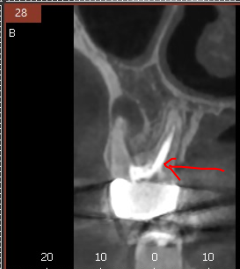

3D ct 등을 통해 정밀한 검사를 진행한 결과,

치아 뿌리 주변의 염증으로 한쪽 뼈를 녹였네요.

ct 상 한쪽 뼈만 녹아있는 상황이라

반대편 뼈에 기대해보면서